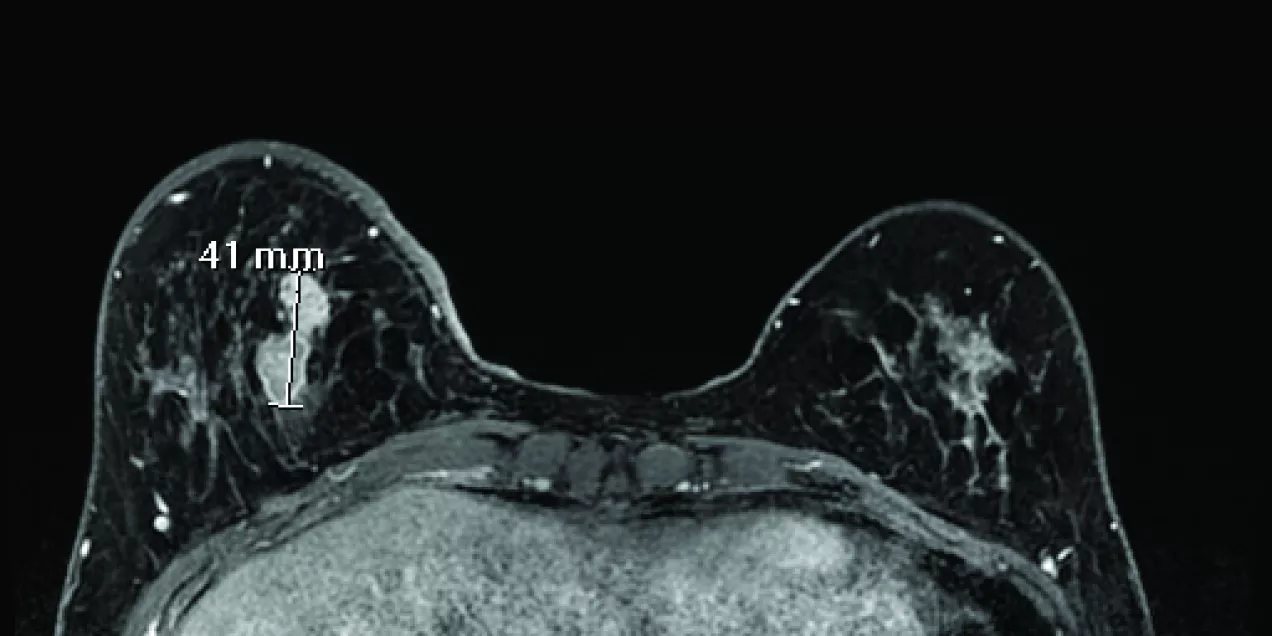

breast MRI scan showing both breasts in axial view with a bright enhancing lesion on the left side marked with a 41 mm measurement indicator, surrounded by fibroglandular tissue against a dark background